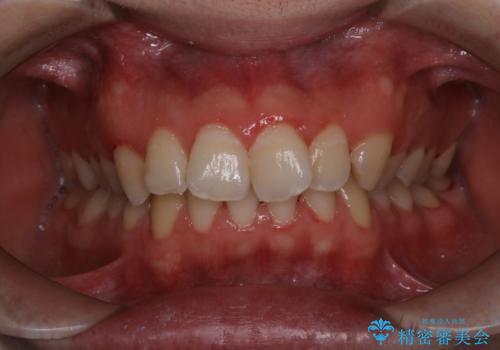

- 今まで歯医者で、クリーニングを受けたことがないため綺麗にしたいとのことでした。PMTC60分コースを行いました。

歯周病とは、細菌による感染症です。歯周病菌を取り除くには、歯周ポケットの中を機械的に掃除することです。

歯周病の原因は、歯にべったりと付着するプラーク(細菌の塊)や歯石です。そこから歯周病菌が引き起こす炎症により、歯を支える歯周組織が破壊され、最終的には歯が抜け落ちてしまうという怖い病気です。

もっとも、効果的な治療法がPMTC(歯科医院で専門的な機械や材料を使用してクリーニング)を定期的に行うことです。